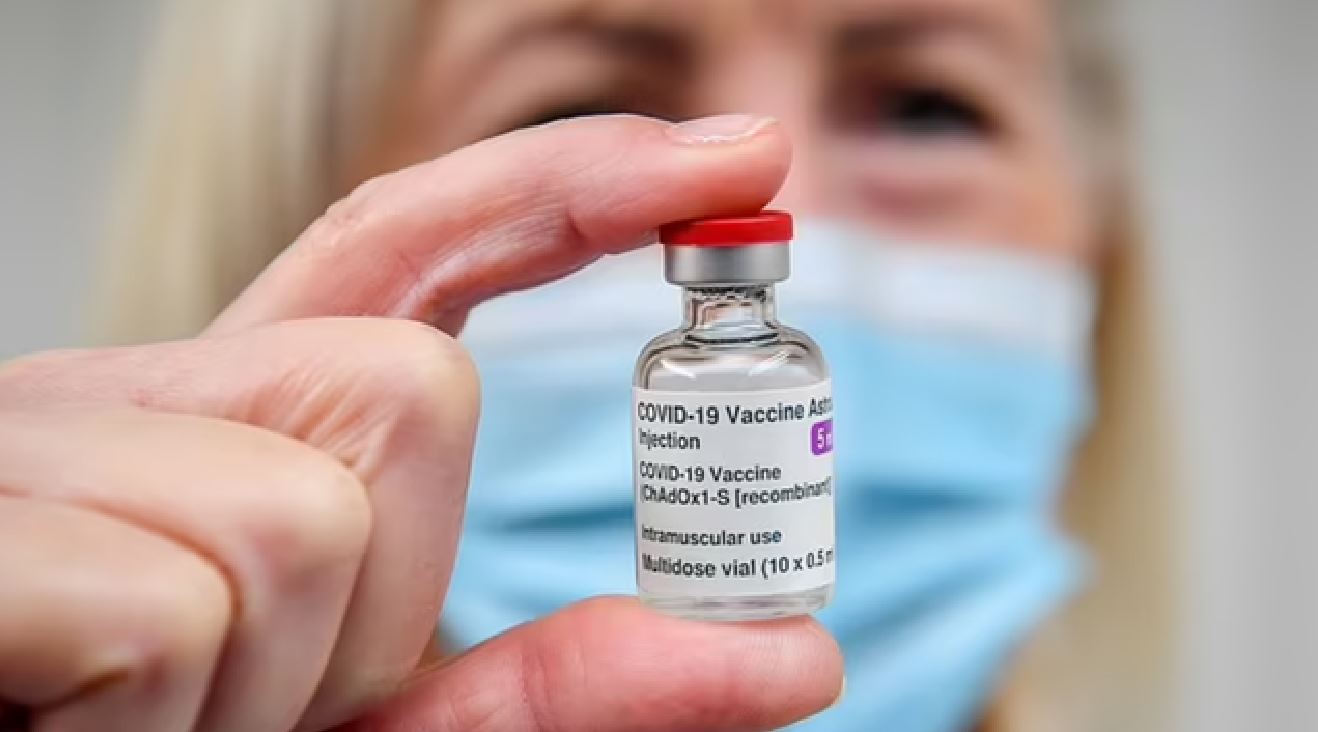

Ekspertët paralajmërojnë se vaksina kundër Covid-it mund të shkaktojë inflamacion vdekjeprurës në tru

Anglia, vendi i parë në botë me vaksinë kundër infeksionit gonorrea

Ekspertët paralajmërojnë se vaksina kundër Covid-it mund të shkaktojë inflamacion vdekjeprurës në tru

Vaksina kundër herpes zosterit (lisë së dhenve) ul rrezikun e sulmit në zemër dhe goditjes në tru

Shkencëtarët zbulojnë efekt anësor të papritur nga vaksina e re mRNA kundër HIV-it

Vaksina kundër grave me efekt tepër negativ tek gratë, zbulojnë shkencëtarët